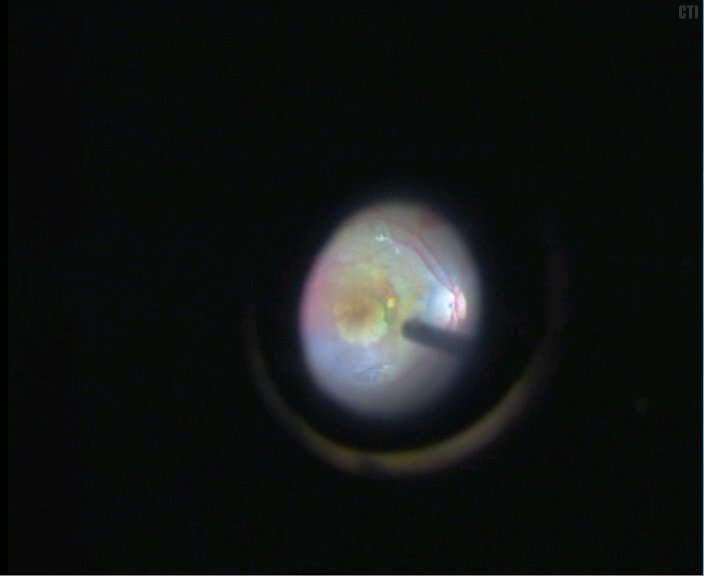

4、取出机化膜可见黄斑区下大片的色素上皮缺损

5、视乳头鼻上房取1.5PD大小的色素上皮组织

光凝供体区域-切开视网膜-切开色素上皮及其下的部分脉络膜组织-切断游离出色素上皮植片

6、将色素上皮植片植入黄斑区下

7、手术结束后可见黄斑区下色素上皮移植片